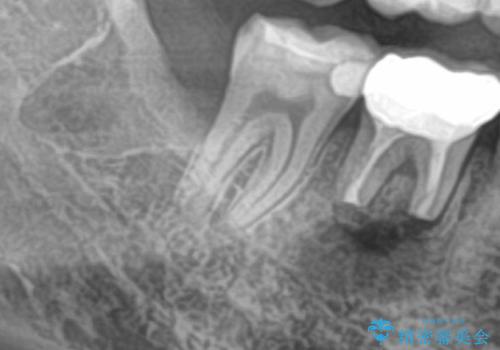

- 右下の親知らずを抜きたいとのことで来院された患者様です。

CTで神経の位置などを確認し、抜歯術を行いました。

しっかり麻酔が効いたことを確認してから安全に抜歯を行いました。